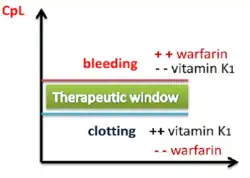

The common side effect, a natural consequence of reduced clotting, is bleeding.[11] Less common side effects may include areas of tissue damage, and purple toes syndrome.[11] Use is not recommended during pregnancy.[11] The effects of warfarin are typically monitored by checking prothrombin time (INR) every one to four weeks.[11] Many other medications and dietary factors can interact with warfarin, either increasing or decreasing its effectiveness.[11][12] The effects of warfarin may be reversed with phytomenadione (vitamin K1), fresh frozen plasma, or prothrombin complex concentrate.[12]

Warfarin decreases blood clotting by blocking vitamin K epoxide reductase, an enzyme that reactivates vitamin K1.[12] Without sufficient active vitamin K1, the plasma concentrations of clotting factors II, VII, IX, and X are reduced and thus have decreased clotting ability.[12] The anticlotting protein C and protein S are also inhibited, but to a lesser degree.[12] It is wrongly described as a "vitamin K antagonist". This term is incorrect. Warfarin does not antagonize the action of vitamin K1, but rather antagonizes vitamin K1 recycling, depleting active vitamin K1. A few days are required for full effect to occur, and these effects can last for up to five days.[11][13] Because the mechanism involves enzymes such as VKORC1, patients on warfarin with polymorphisms of the enzymes may require adjustments in therapy if the genetic variant that they have is more readily inhibited by warfarin, thus requiring lower doses.[14]

Dosing

Dosing of warfarin is complicated because it is known to interact with many commonly used medications and certain foods.[26] These interactions may enhance or reduce warfarin's anticoagulation effect. To optimize the therapeutic effect without risking dangerous side effects such as bleeding, close monitoring of the degree of anticoagulation is required by a blood test measuring an prothrombin time (INR). During the initial stage of treatment, INR is checked daily; intervals between tests can be lengthened if the patient manages stable therapeutic INR levels on an unchanged warfarin dose.[24] Newer point-of-care testing is available and has increased the ease of INR testing in the outpatient setting. Instead of a blood draw, the point-of-care test involves a simple finger prick.[27]

The maintenance dose of warfarin can fluctuate significantly depending on the amount of vitamin K1 in the diet. Keeping vitamin K1 intake at a stable level can prevent these fluctuations. Leafy green vegetables tend to contain higher amounts of vitamin K1. Green parts of members of the family Apiaceae, such as parsley, cilantro, and dill are extremely rich sources of vitamin K; cruciferous vegetables such as cabbage and broccoli, as well as the darker varieties of lettuces and other leafy greens, are also relatively high in vitamin K1. Green vegetables such as peas and green beans do not have such high amounts of vitamin K1 as leafy greens. Certain vegetable oils have high amounts of vitamin K1. Foods low in vitamin K1 include roots, bulbs, tubers, and most fruits and fruit juices. Cereals, grains, and other milled products are also low in vitamin K1.[31]